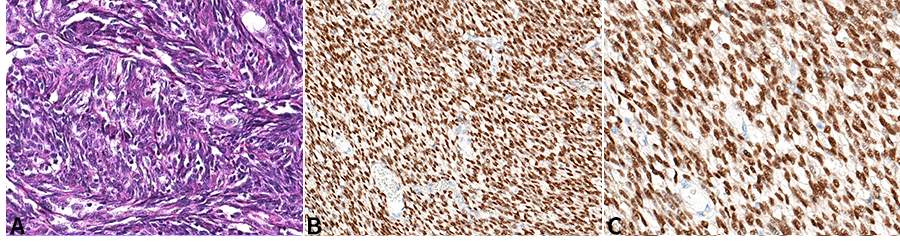

新近研發(fā)的針對SS融合蛋白連接處的特異性抗體SS18-SSX(克隆號E9X9V,圖1,引自參考文獻3)在滑膜肉瘤腫瘤細胞核呈中等至強陽(yáng)性表達(圖2),其靈敏度和特異度分別達95%和100%[3, 4]。研究表明[5],SS18-SSX IHC在診斷SS方面和FISH等分子檢測方法具有很好的一致性(圖3,引自參考文獻5),甚至比其他方法檢測SS更有特異性,特別是在非典型FISH模式的病例中(圖4,引自參考文獻5),它與RNA測序結果有很好的相關(guān)性,有充分的證據說(shuō)明此抗體在診斷SS方面已經(jīng)替代了FISH檢測方法。

圖3.免疫組化染色SS18-SSX(E9X9V)強陽(yáng)性,NGS測序證實(shí)具有滑膜肉瘤特征型的SS18-SSX融合基因(引自參考文獻5)